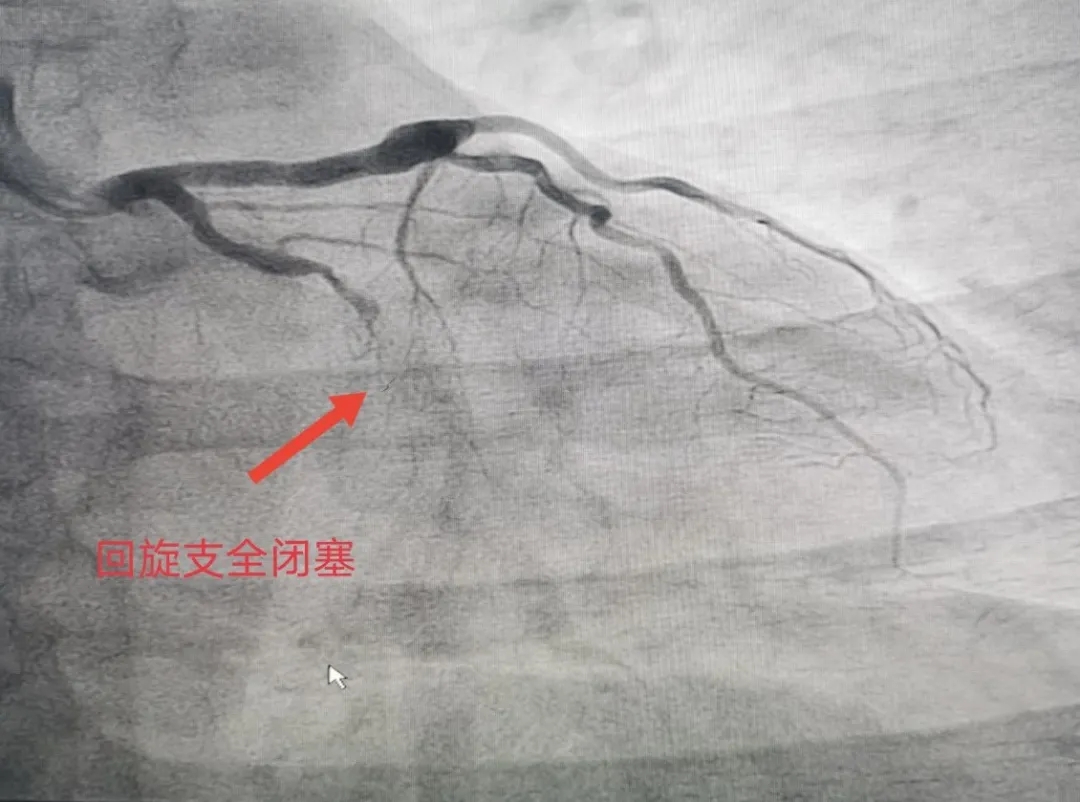

7月19日,前来医院体检的马某在检查冠状动脉造影时,显示左冠右冠分别有不同程度狭窄,冠狭窄50%左右,左回旋支全闭塞。院方立马与家属谈话同意治疗,给予NS导丝很难通过血管,又给予Fielder XT通过,判断出血管钙化严重,放支架不是最好的效果,便实施了PTCA球囊扩张治疗。经过介入团队2个半小时的努力,最终使患者受益,手术当下达到了最好的效果。患者亲属多有心脏搭桥手术,自身支架植入手术后无特殊症状,只是偶尔牙痛放射至心前区不适,本次手术后感觉轻松了很多。

患者术后血流恢复情况